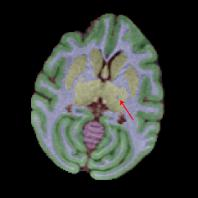

Non-human primates (NHPs) serve as critical models for understanding human brain function and neurological disorders due to their close evolutionary relationship with humans. Accurate brain tissue segmentation in NHPs is critical for understanding neurological disorders, but challenging due to the scarcity of annotated NHP brain MRI datasets, the small size of the NHP brain, the limited resolution of available imaging data and the anatomical differences between human and NHP brains. To address these challenges, we propose a novel approach utilizing STU-Net with transfer learning to leverage knowledge transferred from human brain MRI data to enhance segmentation accuracy in the NHP brain MRI, particularly when training data is limited. The combination of STU-Net and transfer learning effectively delineates complex tissue boundaries and captures fine anatomical details specific to NHP brains. Notably, our method demonstrated improvement in segmenting small subcortical structures such as putamen and thalamus that are challenging to resolve with limited spatial resolution and tissue contrast, and achieved DSC of over 0.88, IoU over 0.8 and HD95 under 7. This study introduces a robust method for multi-class brain tissue segmentation in NHPs, potentially accelerating research in evolutionary neuroscience and preclinical studies of neurological disorders relevant to human health.